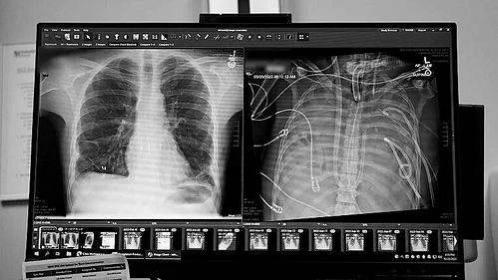

《自然》(Nature)杂志头条刊发美国西北大学医学院安基·巴拉特(Ankit Bharat)团队的一项重磅“人工肺”研究:一名33岁男性因重症流感引发急性呼吸窘迫综合征,双肺出现化脓性坏死,为防止多器官衰竭,需紧急切除双肺并等待移植。借助人工肺系统,该患者在无肺状态下安全存活48小时,随后成功接受双肺移植手术。术后近三年随访显示,患者未发生排异反应,心肺功能正常,生活质量已接近同龄健康人。

《自然》(Nature)杂志头条刊发美国西北大学医学院安基·巴拉特(Ankit Bharat)团队的一项重磅“人工肺”研究:一名33岁男性因重症流感引发急性呼吸窘迫综合征,双肺出现化脓性坏死,为防止多器官衰竭,需紧急切除双肺并等待移植。借助人工肺系统,该患者在无肺状态下安全存活48小时,随后成功接受双肺移植手术。术后近三年随访显示,患者未发生排异反应,心肺功能正常,生活质量已接近同龄健康人。